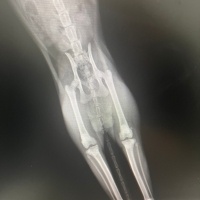

Merhabalar, sekiz aylık kedimin yüksekten düşme sebebiyle sağ arka bacagı kırıldı. Veterinerimiz bir haftalık kafes istirahati ve kalsiyum takviyesi ile kayanayabilecegini söyledi. Hem genç oldugu için hemde kırık çok ayrılmadıgı için. Kalsiyum kaici kedi yogurdu, vitamin malt, kemik iliği suyuyla destekliyorum. Ödül mamalarını falan reddetmiyor mamasını da yiyor ama suyun yüzüne bile bakmıyor. Kaşıkla diline bırakıyorum öyle içiyor. Başına gelen var mı bilmiyorum ama hem kırıkla ilgili yorum hemde su konusunda tavsiyesi olan var mıdır? Fotograf ekliyorum